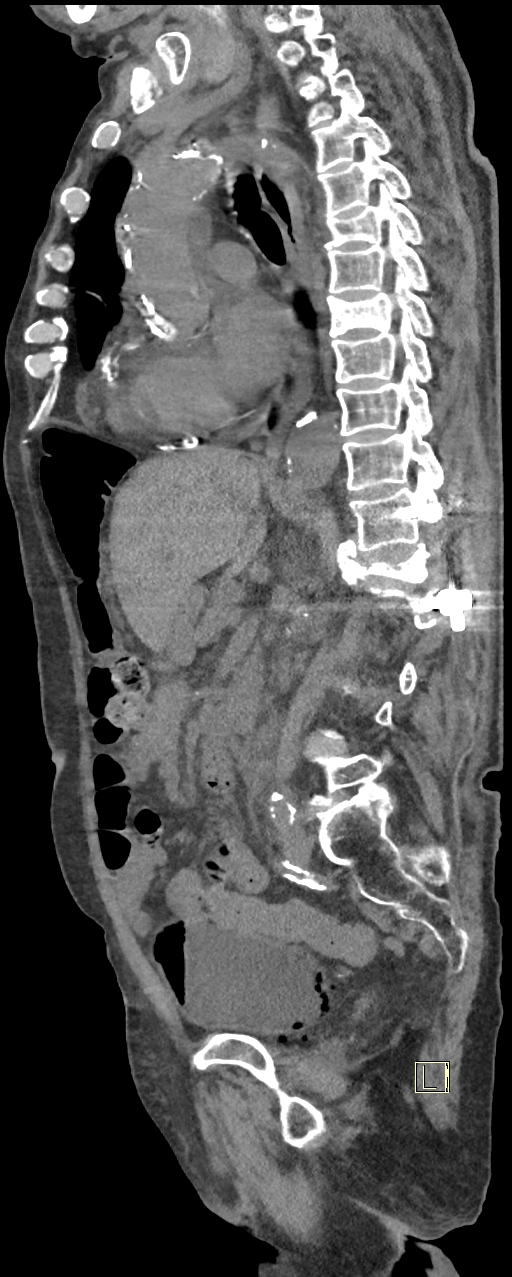

CAZ nr 131: Cistită emfizematoasă

Figurile 3 şi 4: sagital examinare CT abdomen şi pelvis fără substanță de contrast

Discuţie caz nr 131: pacient de 85 de ani cunoscut diabetic este adus la camera de gardă pentru dureri abdominale difuze, efectueaza CT fără substanță de contrast deoarece eGFR este 21 mL/min/1.73 m². Se evidențiază pericardita în cantitate medie, mai multe chiste renale – unul spontan hiperdens, multiple plăci aterotrombotice calcificate la nivelul aortei și ramurilor precum și multiple bule aerice în peretele vezicii urinare și conținut hidro-aeric al vezicii urinare. Ultimele două elemente sugerează diagnosticul de cistita emfizematoasă.

DE LUAT ACASĂ!!! Cistita emfizematoasă este o infecție gravă, dar rară, a vezicii urinare, în care bacteriile producătoare de gaze creează bule de aer în peretele vezicii urinare, adesea asociate cu diabetul necontrolat, mai rar cu utilizarea cateterului sau vezica urinară neurogenă. Simptomele includ dureri abdominale inferioare, febră și urinare dureroasă sau frecventă, dar diagnosticul necesită tomografie computerizată pentru a observa gazele. Tratamentul implică antibiotice și gestionarea afecțiunilor subiacente, fiind posibil necesară intervenția chirurgicală în cazurile severe, deși tratamentul prompt duce de obicei la un rezultat favorabil.